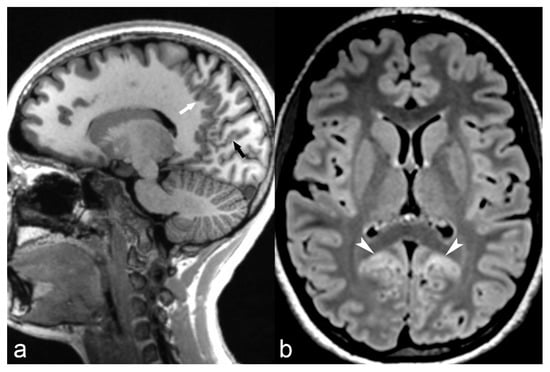

Classical lissencephaly is characterized by reduced or absent gyri associated with a thickened cortex and shallow sulci. Microscopically, the cortex lacks the normal lamination and consists of only 4 layers instead of the typical 6 layers. Macroscopically, the sylvian and Rolandic fissures are poorly developed and there is a failure of operculization of the insular areas [85]. This results in a smooth appearance of the brain surface with the characteristic “Figure 8” or “hourglass” shape of the brain in axial images (Figure 6) [83]. There are several gene mutations implicated in its pathogenesis and a wide spectrum of clinical manifestations such as severe intellectual disability, hypotonia and epilepsy. It is usually diagnosed early in life, although mild cases may have delayed presentation [69]. Miller-Dieker syndrome (MDS) is a severe form of classical lissencephaly associated with facial dysmorphism and occasionally other congenital abnormalities, epilepsy and a severely shortened life expectancy, related to a chromosome 17 gene deletion. Cobblestone lissencephaly is a distinct form of lissencephaly characterized by a nodular appearance of the brain cortex secondary to abnormal organization of the cortical layers.

Figure 6.

6-month-old baby. Axial T2WI slices through the lateral ventricles (a) and occipital lobes (b) demonstrate a distinct lack of normal brain gyration with a smooth and thickened appearance of the cortex and unfolded gyri, most pronounced in both parietal, temporal and occipital lobes (arrows) consistent with lissencephaly. Note the posterior-anterior gradient with some rudimental sulcation seen in the frontal lobes. Band heterotopia can be clearly seen in the parietal regions on sagittal T1 IR (c) with cobblestone appearance (arrow).